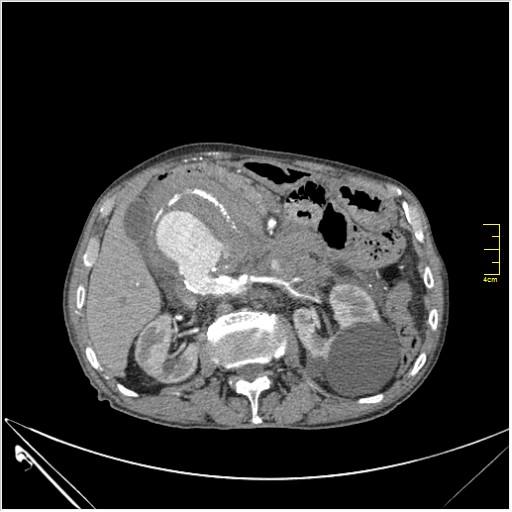

КТ брюшной полости. Мужчина с пальпируемой опухолью в животе

Пациент Т. 64 года, обратился на КТ брюшной полости амбулаторно (!), по направлению семейного врача с диагнозом abdominal mass, буквально: образование брюшной полости.